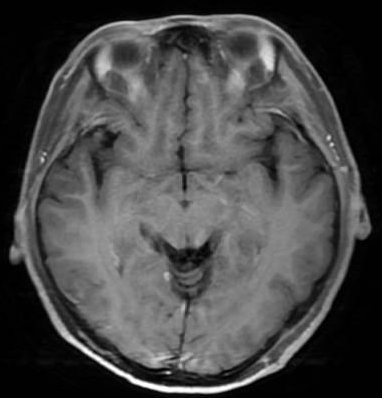

颅脑MR:双侧大脑半球脑回表面及小脑幕区见多发强化结节灶,最大约5mm×4mm,考虑肿瘤转移;小脑及脑干形态、信号未见明显异常;中线结构居中,各脑室系统无扩张,脑沟、脑裂无增宽。颈椎及顶骨骨质呈不均匀异常强化,考虑骨转移。

治疗仅8周后,复查胸CT、腹盆CT、头MR、肿瘤标志物,评效结果为缩小的SD,肿瘤标志物下降,肝功能恢复正常。基线27mm的肺部病灶在持续治疗中不断缩小,至2025年4月CT复查完全消失,并维持至今。脑转移灶5mm缩小至2-3mm。